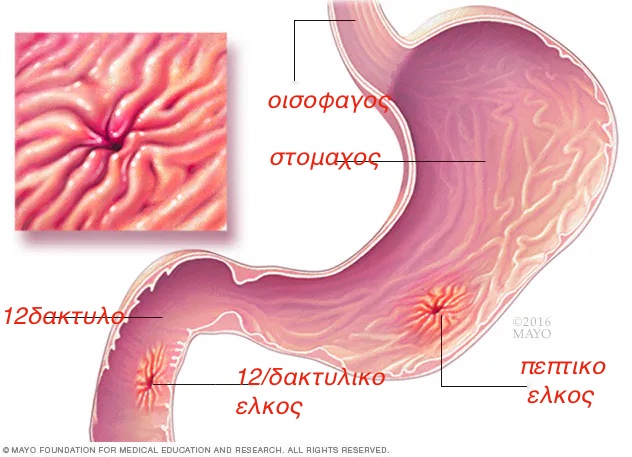

πεπτικο ελκος

Πρόκειται για διάβρωση της βλενογονιας στιβάδας η και της υποβλενογονιας η μυικης στιβάδας .Διαταραχές μεταξύ έκκρισης οξέος και γαστρινης καθώς και των αμυντικών μηχανισμών του βλενογονου δημιουργούν το έλκος.

Πάντα πρέπει να λαμβάνεται υπόψη η πιθανότητα ύπαρξης κακοήθειας ,γι'αυτο τον λόγο να λαμβάνονται βιοψίες από τον πυθμένα του έλκους.

Το ελικοβακτηρίδια του πυλωρου ,τα μη στεροειδή αντιφλεγμονώδη φάρμακα και οι συνήθειες του τρόπου ζωής (stress,αλκοολ) αυξάνουν τις πιθανότητες δημιουργίας του έλκους.

Επιγασρικος καυσος(καούρα),επιγαστραλγια.Η λήψη τροφής επιδεινώνει τα συμτωματα στο γαστρικό έλκος ένα απαλύνει τον πόνο στο δωδεκαδακτυλικο έλκος.

Ο πόνος μπορεί να συνοδεύεται από εμετούς ,ναυτία η και απώλεια βάρους.